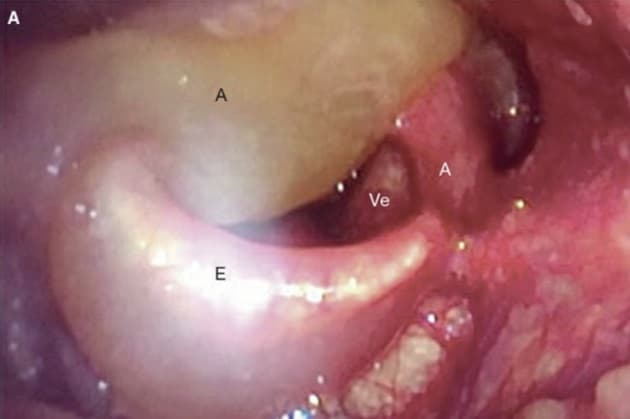

Fleksibel laryngoskopi umiddelbart efter indlæggelse.

Medicinsk anvendelse af lattergas udnytter den kortvarige sedative og analgetiske effekt i forbindelse med f.eks. tandindgreb og ved fødsler. Over de seneste år er lattergas blevet et udbredt rusmiddel. Kasuistikken af Thorsberger og Aanæs beskriver udvikling af ødem i hypopharynx og larynx, formentligt udløst af frysningsskade efter inhalation af store mængder lattergas under højt tryk.